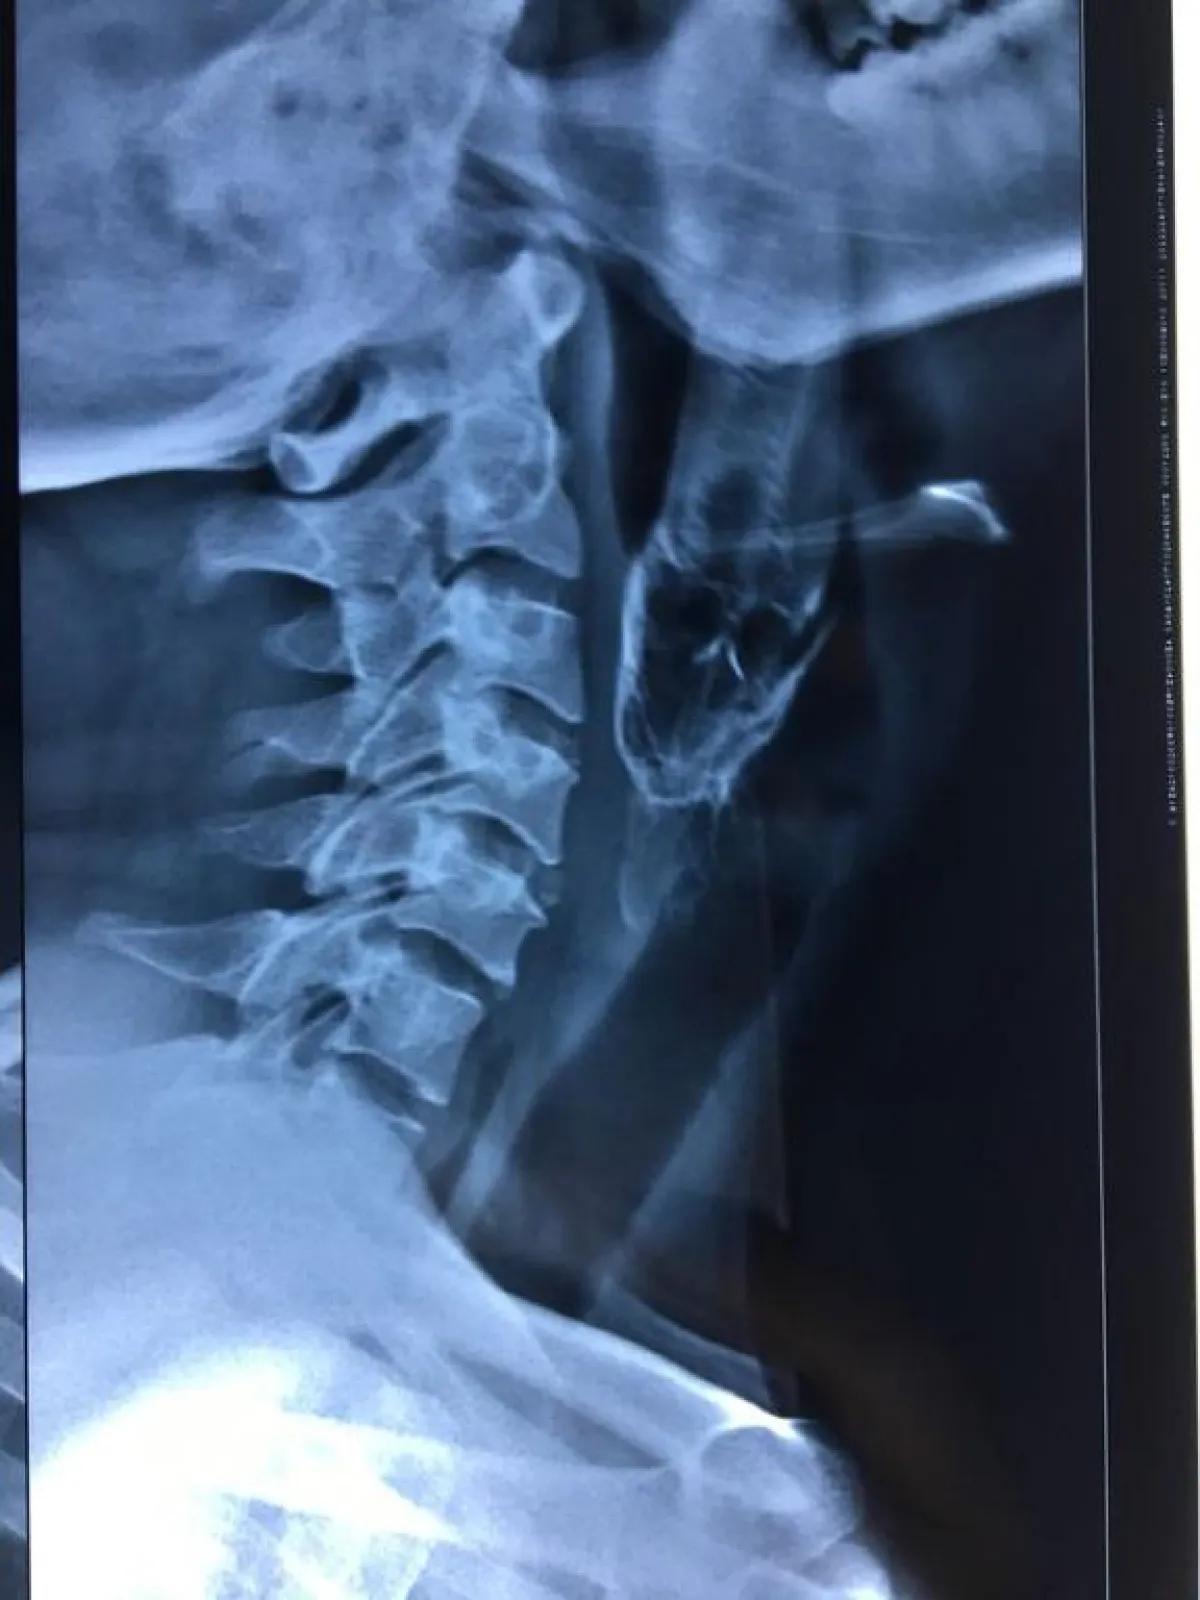

وتم نقله إلى المستشفي فى مدينة «بهوانشوار» حيث خضع إلى جراحة عاجلة، واستخدم الأطباء «ملقاط» لسحب السمكة التي تسببت فى تمزقات داخل حلق الصياد بسبب زعانفها، وكان لا يظهر من السمكة سوى جزء صغير من ذيلها عبر الحلق. فيما تم إبقاء المريض على أجهزة التنفس الصناعي لمدة 10 أيام حتى تعافى تمامًا وعاد إلى منزله.